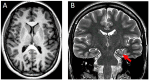

Case presentation: We report a 19-year-old female with a de novo heterozygous variant in ZMYM3 (NM_201599.3:c.1927C>G, p.(His643Asp)), presenting with ADHD symptoms, poor motor coordination, and mild cognitive impairments. Although her language development was normal, she exhibited motor delays, learning and social difficulties, leading to anxiety and academic struggles. Neuropsychological assessment revealed an IQ of 85, with significant deficits in working memory and visuospatial reasoning but relative strengths in verbal comprehension. Brain MRI showed an incomplete left-sided hippocampal inversion. Genetic analysis confirmed the presence of the ZMYM3.